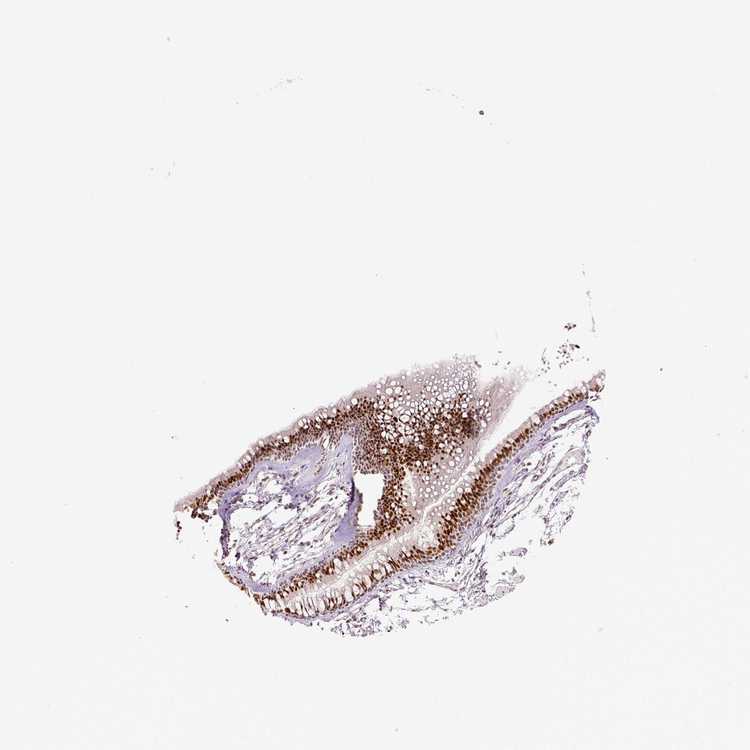

SOFT TISSUE 1 - Antibody stainingi

Antibody staining in the annotated cell types in the current human tissue is reported as not detected, low, medium, or high, based on conventional immunohistochemistry profiling in selected tissues. This score is based on the combination of the staining intensity and fraction of stained cells.

Each image is clickable and will lead to virtual microscopy that enables deeper exploration of all samples and also displays staining intensity scores, fraction scores and subcellular localization as well as patient and tissue information for each sample.

Antibody HPA029773Antibody CAB004390Antibody CAB072859Antibody CAB072860

Fibroblasts MediumMediumMediumMedium

Peripheral nerve -Medium--